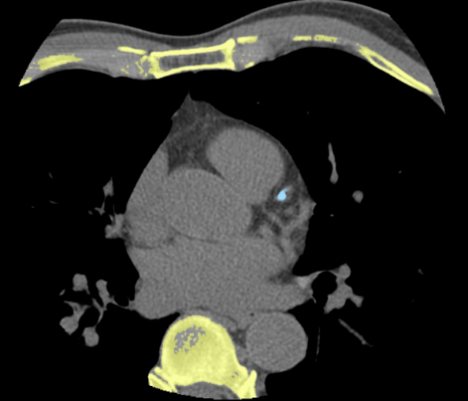

大范围胸痛三联征一次扫描完成图像采集,同时配置宽体能谱成像+16厘米容积灌注成像+40厘米大范围动态成像多种成像方式选择为临床带来更加精准诊断

联影ct怎么样【小南快讯】辐射低、成像快、更精确!CT届的“天花板”——320排640层超高端CT落户奉中心!_https://www.jmylbn.com_新闻资讯_第16张